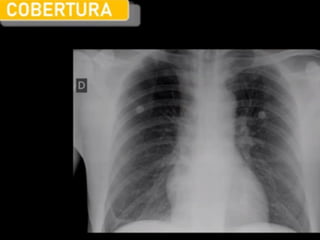

1.Derrame pleural

Acumulación (4) de líquido (exudado/trasudado) en la cavidad

pleural (2) entre pleural parietal (1) y visceral (3).

• Opacidad homogénea densa.

• Pérdida del ángulo costofrénico.

• Aspecto de menisco (↑ alto lateral que medial, borde superior

cóncavo)

• Borramiento del hemidiafragma.

• Sin broncograma aéreo.